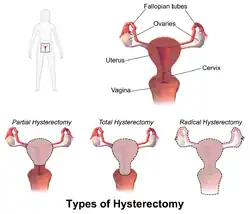

Types

Hysterectomy, in the literal sense of the word, means merely the removal of the uterus. However, other organs such as the ovaries, fallopian tubes, and the cervix are very frequently removed as part of the surgery.[60]

- Radical hysterectomy: complete removal of the uterus, cervix, upper vagina, and parametrium. Indicated for cancer. Lymph nodes, ovaries, and fallopian tubes are also usually removed in this situation, such as in Wertheim's hysterectomy.[61]

- Total hysterectomy: complete removal of the uterus and cervix, with or without oophorectomy.

- Subtotal hysterectomy: removal of the uterus, leaving the cervix in situ.

Subtotal (supracervical) hysterectomy was originally proposed with the expectation that it may improve sexual functioning after hysterectomy, it has been postulated that removing the cervix causes excessive neurologic and anatomic disruption, thus leading to vaginal shortening, vaginal vault prolapse, and vaginal cuff granulations.[62] These theoretical advantages were not confirmed in practice, but other advantages over total hysterectomy emerged. The principal disadvantage is that the risk of cervical cancer is not eliminated, and women may continue cyclical bleeding (although substantially less than before the surgery). These issues were addressed in a systematic review of total versus supracervical hysterectomy for benign gynecological conditions, which reported the following findings:[63]